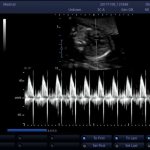

• Пройти ЭКГ;